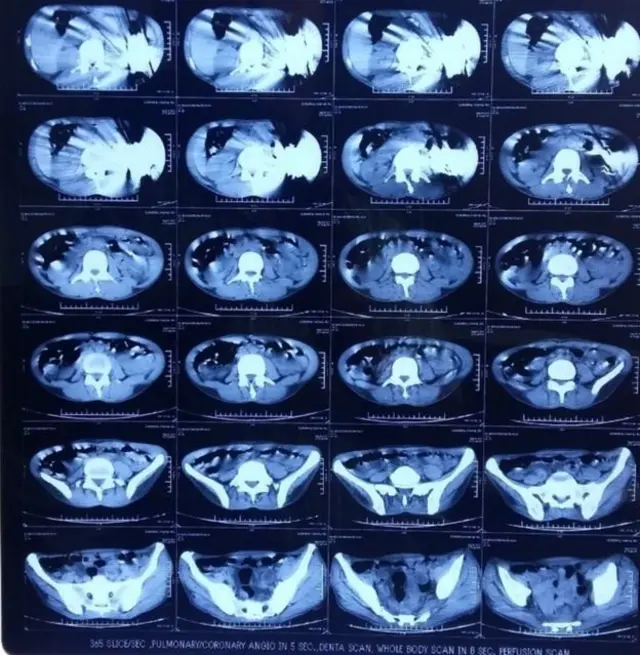

Madaktari katika mji wa Amritsar kaskazini mwa India wamesema, wametoa visu 40 kutoka kwa tumbo la mwanamume mmoja.

Mwanamume huyo mwenye umri wa miaka 42 alikuwa amevimeza visu hivyo kwa muda wa miezi mitatu.

Operesheni hiyo iliwahusisha madaktari watano na ilichukua saa tano kukamilika